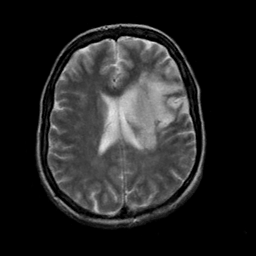

In this paper, we propose a bidirectional learning model, known as dual contrast cycleGAN (DC-cycleGAN), for medical image synthesis from unpaired data. Specifically, a dual contrast (DC) loss is formulated that leverages the advantage of samples from the source domain as negative samples to indirectly build constraints between real source and synthetic images via discriminators, and synthesize images more related to the target domain by enforcing the synthetic images to fall far away from the source domain. In addition, structural similarity index (SSIM) [35] and cross-entropy (CE) [48] are integrated into the DC-cycleGAN structure to avoid disappearing gradient information that is caused by a mean absolute error (MAE) and synthesizing irrelevant images. SSIM considers luminance [35] and CE converges fast as its back-propagation error is less than MSE [28]. As can be seen in Figs. 1 and 2, using SSIM and CE with dual contrast can generate more clear and accurate MR images as compared with that of MAE and MSE, and SSIM and CE without dual contrast loss. Although both SSIM and CE with dual contrast and without dual contrast generate similar CT images, SSIM and CE with dual contrast quantitatively generate better images as shown in Table 4. The experimental results indicate that DC-cycleGAN is able to consider more complex features such as structure in synthesizing images and produce remarkable results as compared with other state-of-the-art methods reported in the literature.

Tables 3 and 4 show the results of MR and CT synthesis, respectively. As can be seen, all components play vital role in both tables. SSIM & CE (w) performs significantly better than other losses in synthesizing MR images. This also can be seen visually in Fig. 1. In contrast, SSIM&CE (w) performs slightly better than SSIM&CE (wo) in synthesizing CT images, both generate more or less similar CT images (see Table 4).